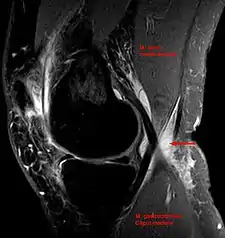

- Baker's cyst on axial MRI with communicating channel between the semimembranosus muscle and the medial head of the gastrocnemius muscle.